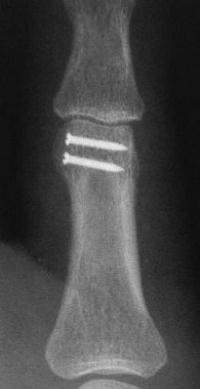

Clinical Example: Unicondylar proximal phalanx head fracture with micro screws

Unicondylar fractures of the phalangeal head are common, frequently unstable and unacceptably displaced. Although some may be treated successfully with percutaneous reduction and fixation, many require open reduction. In these cases, the screws were put right through the collateral ligament and sunk into the cortex. I think the simplest way to do this is to reduce and stabilize with two K wires, then remove the wires and replace with screws, one at a time, so reduction is maintained throughout. 1mm=39/1000" Kwire, so doing the math, here is how you choose the right sized Kwire to use as both drill and provisional fixation:

With two screws, bicortical fixation is not needed. The video below illustrates the steps involved, which are the same with either open or percutaneous fixation.